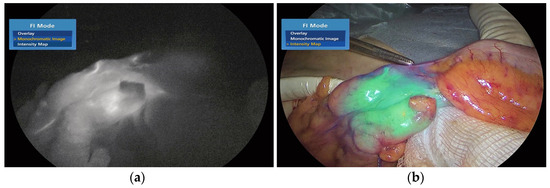

- Lobbes, L.A.; Berns, S.; Warschkow, R.; Schmidt, L.R.; Schineis, C.; Strobel, R.M.; Lauscher, J.C.; Beyer, K.; Weixler, B. Perfusion Visualization during Ileal J-Pouch Formation—A Proposal for the Standardization of Intraoperative Imaging with Indocyanine Green Near-Infrared Fluorescence and a Postoperative Follow-Up in IBD Surgery. Life 2022, 12, 668. [Google Scholar] [CrossRef]

- Spinelli, A.; Carvello, M.; Kotze, P.G.; Maroli, A.; Montroni, I.; Montorsi, M.; Buchs, N.C.; Ris, F. Ileal pouch–anal anastomosis with fluorescence angiography: A case-matched study. Color. Dis. 2019, 21, 827–832. [Google Scholar] [CrossRef]